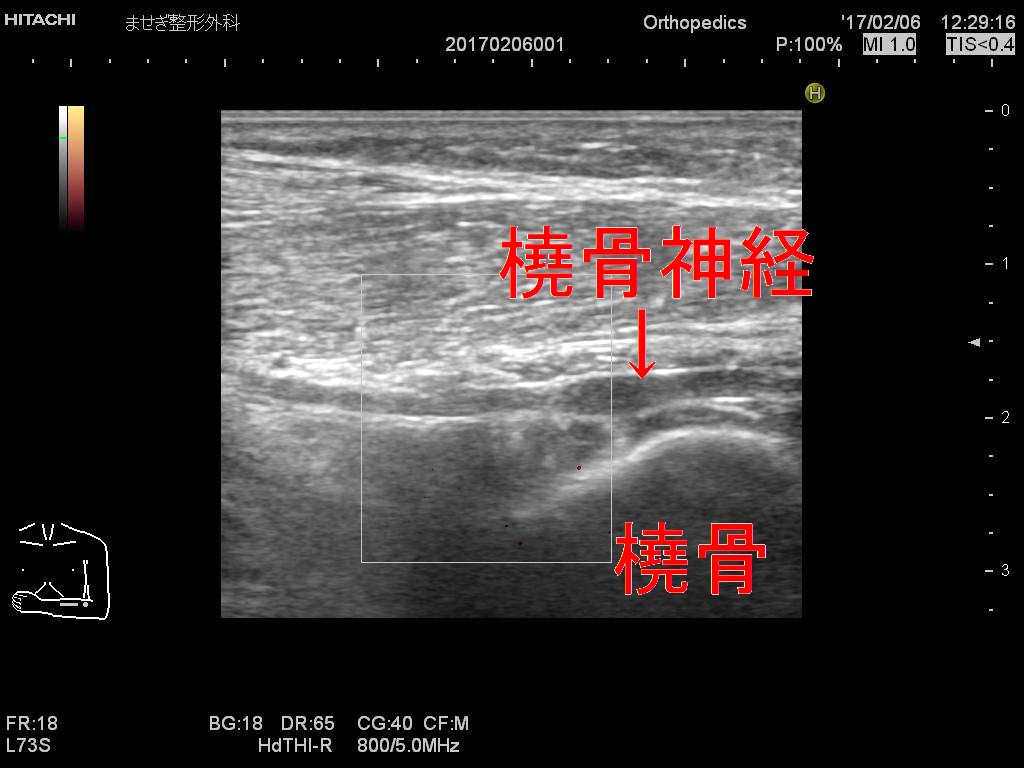

この部位を見てみますと

低エコーで2倍以上に腫大した橈骨神経が観察されました。

ドプラーを入れましたが血管ではありませんので血流なしです。

黒い塊が移動してますがこれが橈骨神経です。強い圧痛もあり炎症も十分考えられます。